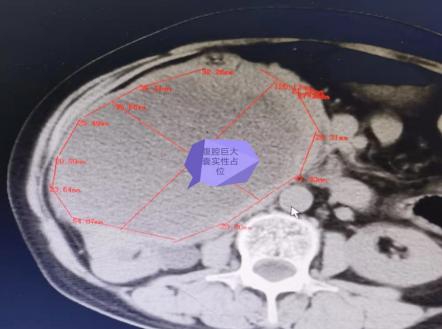

于是,张奶奶来到了长沙进一步确诊,通过 B 超及 CT 检查发现,莫奶奶肚子里长了一个足球大小的肿瘤,压迫影响到了胃,因此,张奶奶才腹胀明显;肿瘤越长越大,上顶到膈肌上了,出现了呼吸困难!于是,经过多学科讨论,任斗教授和普外科曾晓晨主任赶紧决定为其实施手术切除治疗。经过周密的术前准备,腊月 25,通过长达 8 小时的手术,奶奶的巨大肿瘤终于被完整的剥离切除了,这一称重,足足 10 斤!当切下来的肿瘤摆在家人面前的时候,家属也难以置信!